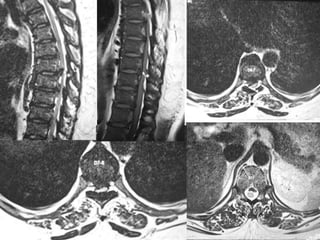

• X-ray of Chest.

• X- Both fore arms - AP

• MRI of Dorsal and Lumbar Spine.

Case report –cont…. • X-ray of Chest. • X- Both fore arms - AP • MRI of Dorsal and Lumbar Spine. • CBC, serum Creatinine, TSH, PTH, Ca, Alk Po4, Urine routine.